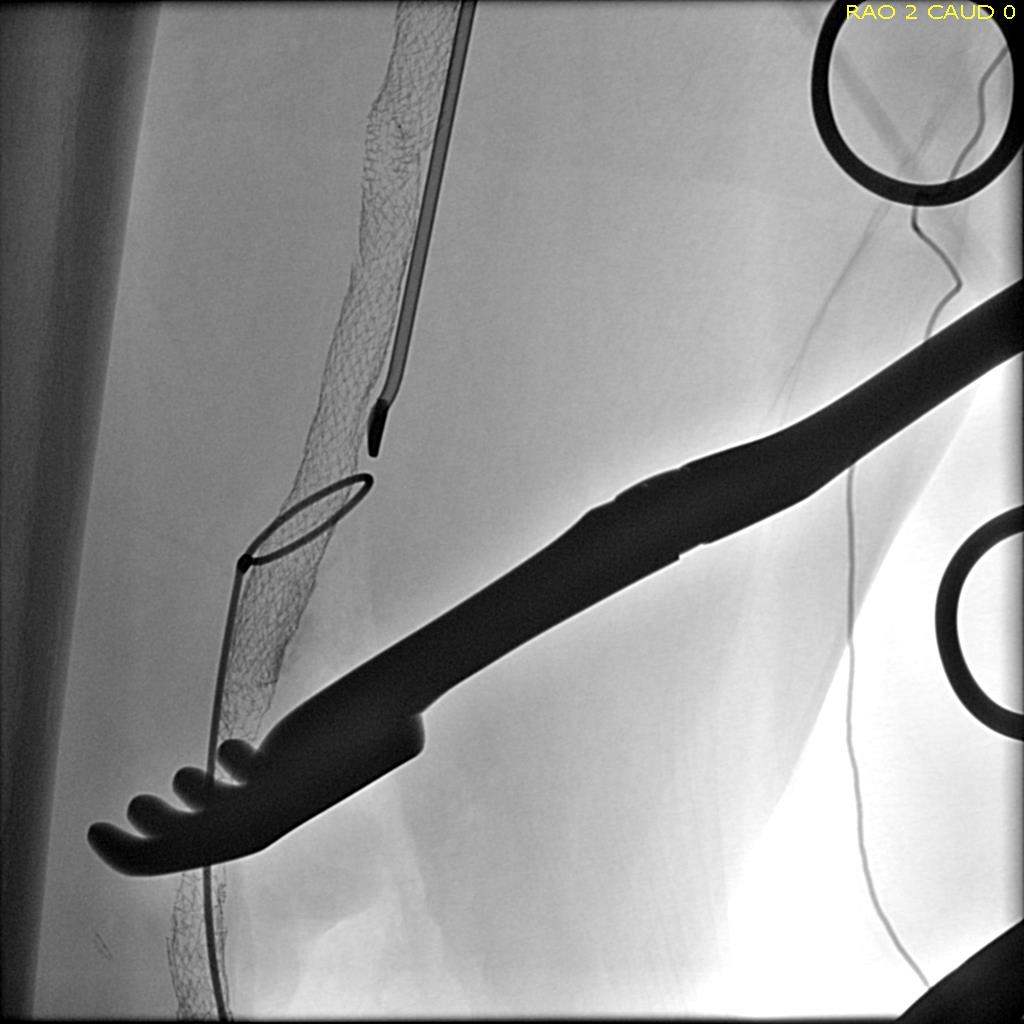

I contacted LeMaitre Vascular and got in touch with your representative, L. Fisher, who promptly sent the Moll Ring Cutters I needed to perform a remote endarterectomy of the patient’s occlusive external iliac and superficial femoral artery plaque. The technical details of remote endarterectomy are have been covered in my blog (https://vascsurg.me/?s=endore), but in the end, through a 7cm incision in the groin (don’t believe the hype, this is minimally invasive), I restored his arteries to their original open condition. Shown below are the results. It was with great sadness that I heard that the LeMaitre Vascular equipment being sent were the last of the stock available in North America. The patient did very well, with the operation completed well before lunch, and is recovering rapidly from his small wound and big rescue. He gets to walk out of the hospital on two legs, but also with the surety that he avoided a major bypass operation, and avoided the short term gains of stenting from the aorta to the profunda -more peel packs and landfill items and a dubious long term durability. Hey, I even used a XenoSure patch on the common femoral.